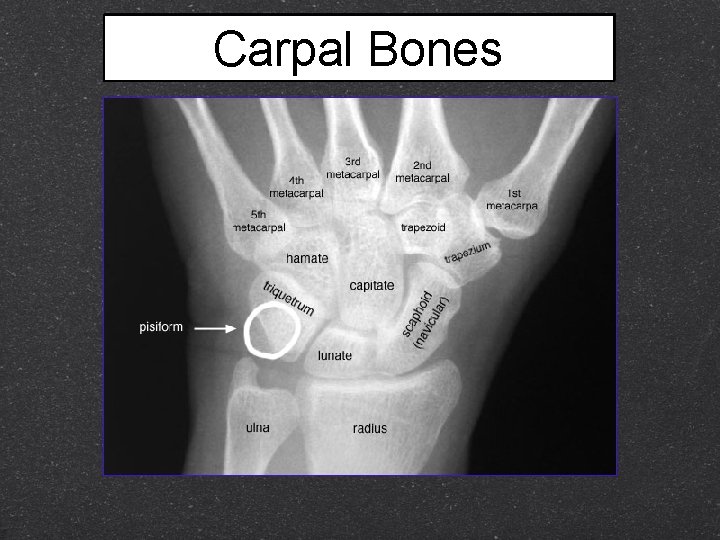

Carpal Bones Eight total Two rows Proximal (closer to the body) Distal (further from the body)

Carpal Bones (proximal row) 1. Scaphoid anatomical snuff box (boat shaped) articulates with radius 2. Lunate (moon shaped) articulates with radius 3. Triquetrum (Triquetral, Cuniform) articulates with radius 4. Pisiform (pea like) Compare to Fig 7. 1 (base of the hypothenar eminence; on top of triquetrum)

Carpal Bones (distal row) 1. Trapezium (Multagulum major) articulates with 1 st MC 2. Trapezoid (Multagulum minor) smallest of second row articulates with 2 nd MC 3. Capitate (Os Magnum) Largest carpal bone Articulates with 3 rd MC) 4. Hamate (Unciform, hook like) (Articulates with 4 th and 5 th MC) Compare to Fig 7. 1